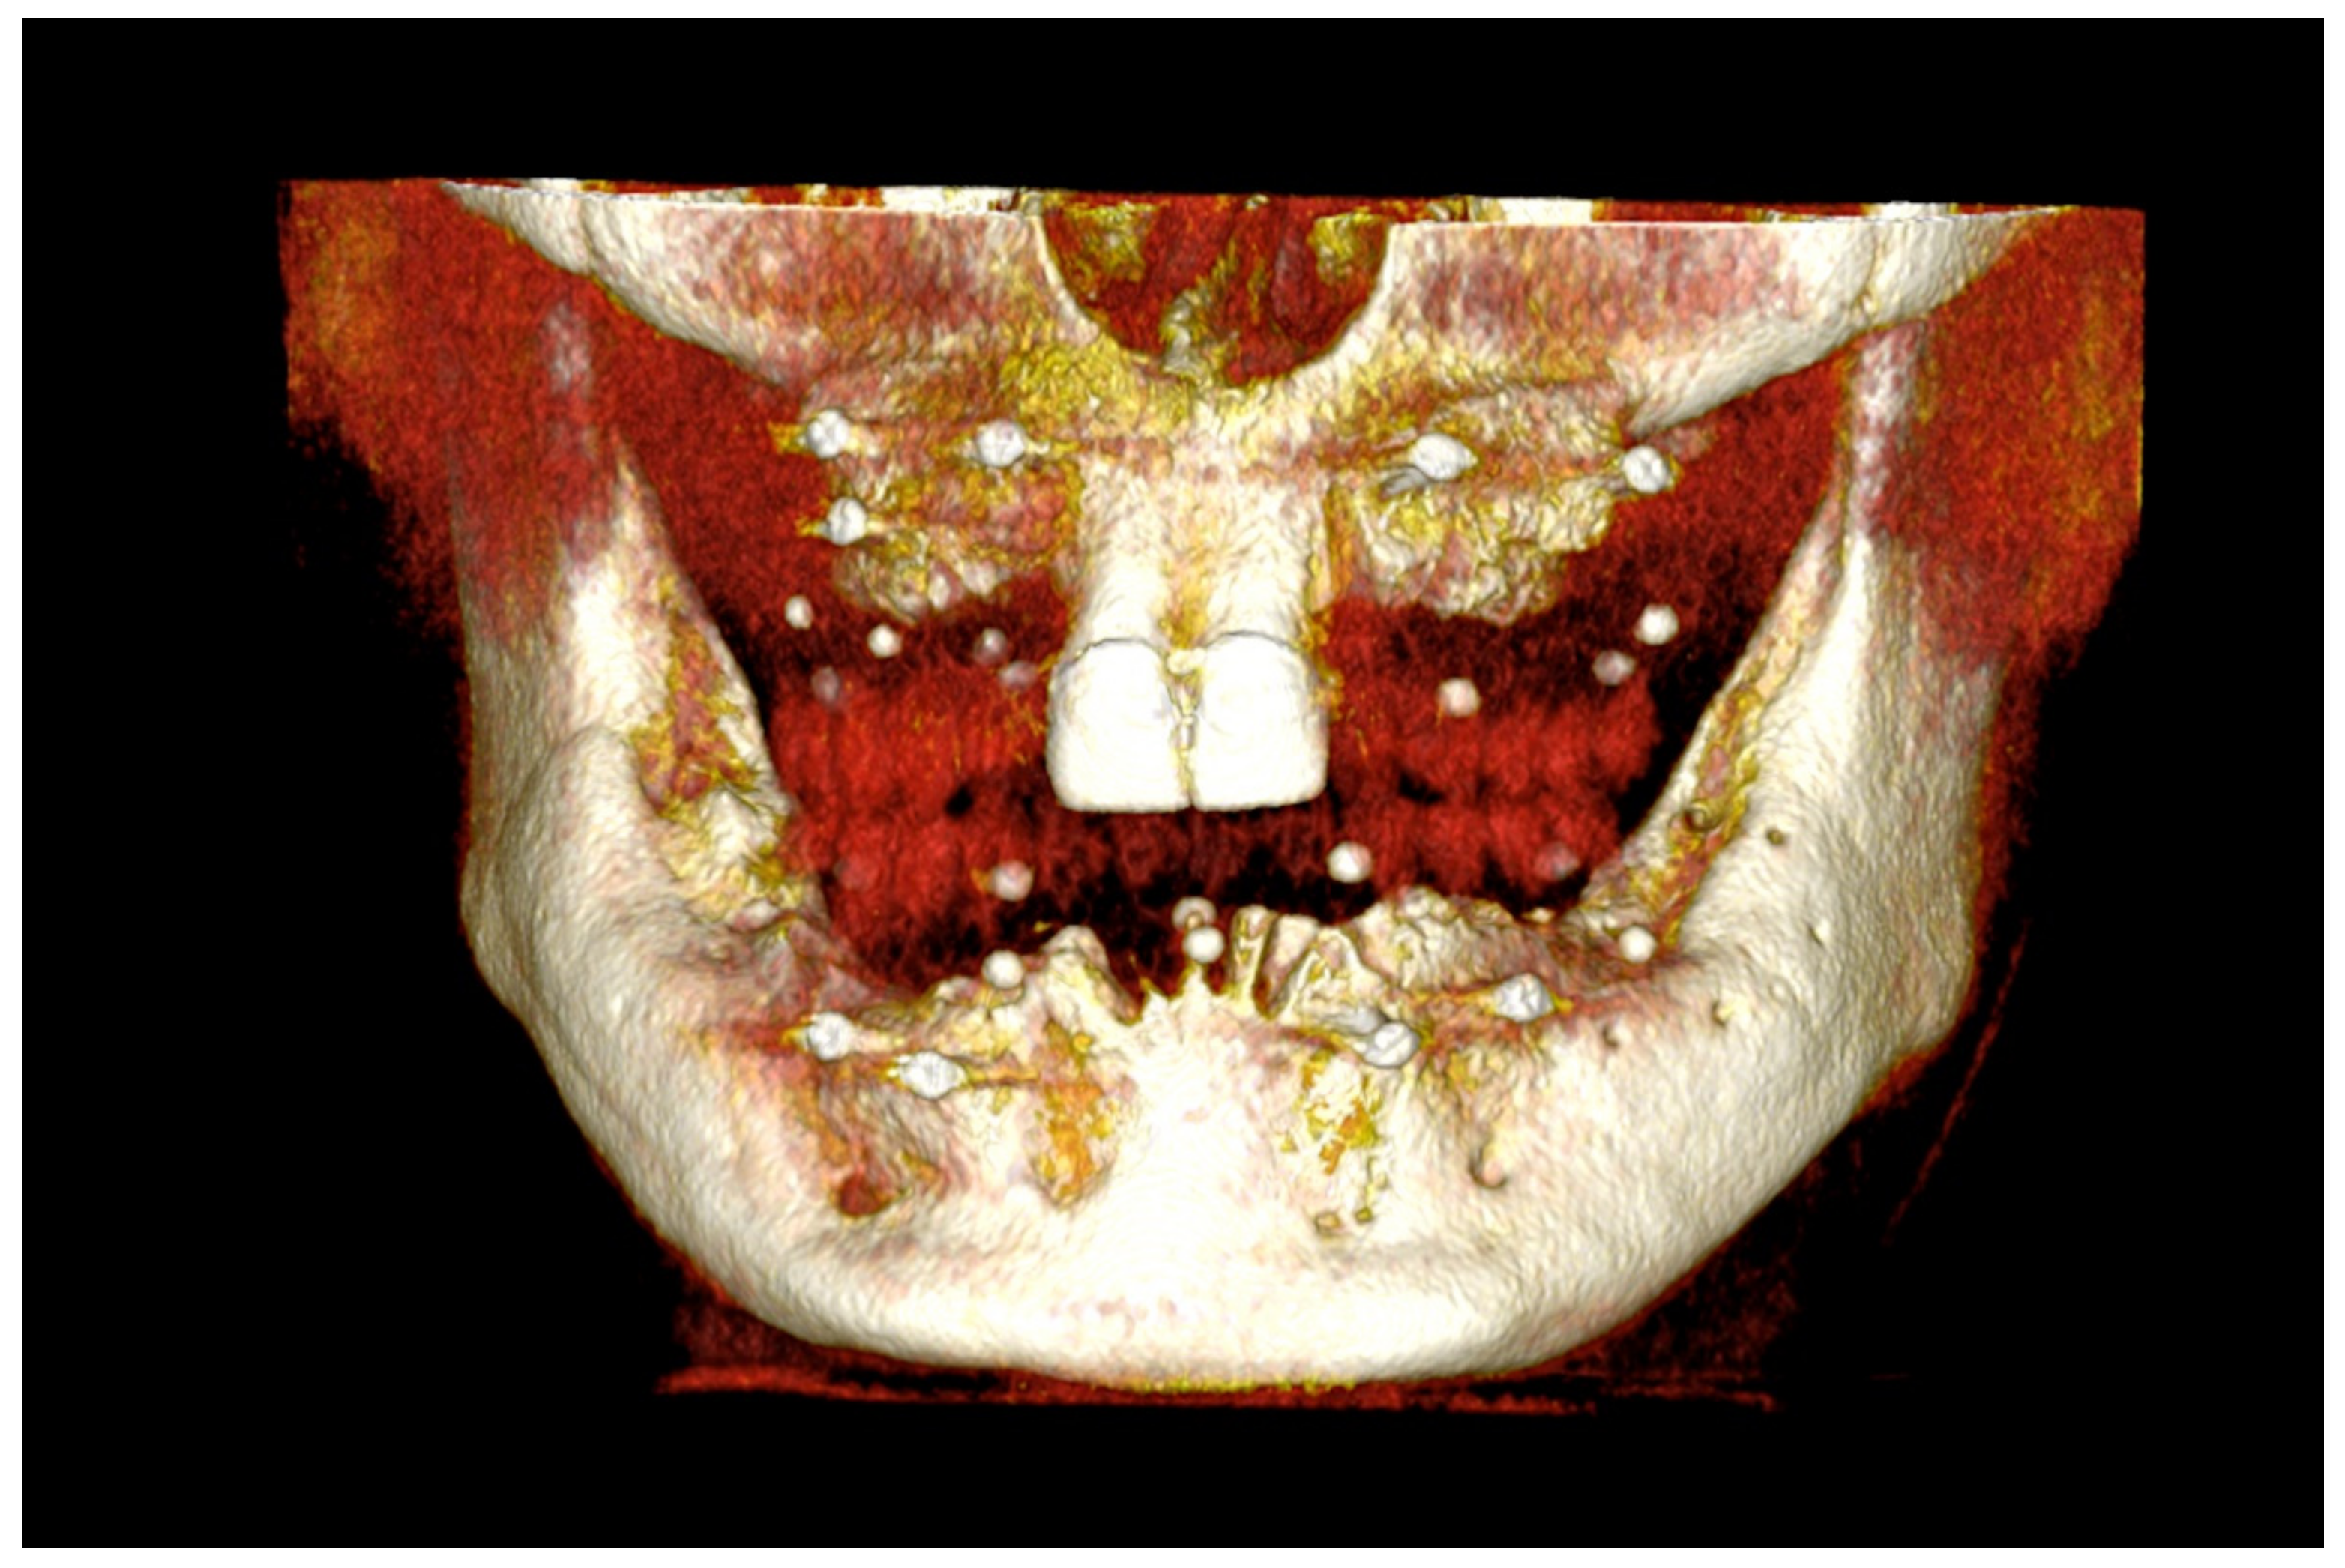

6.2.2. Preoperative Documentation

6.3.2. Preoperative Documentation: